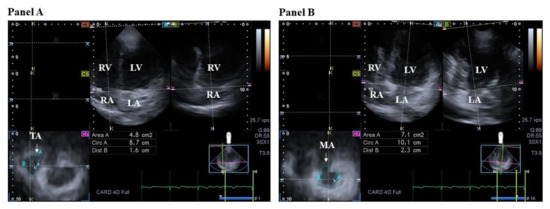

3.3. Mitral Valve

3.3.1. Under Healthy Circumstances

3.3.2. In Acromegaly

- Nemes, A.; Kormányos, Á.; Domsik, P.; Kalapos, A.; Lengyel, C.; Ambrus, N.; Valkusz, Z. Mitral annulus is dilated with preserved function in acromegaly regardless of its activity: Insights from the three-dimensional speckle-tracking echocardiographic MAGYAR-Path Study. Rev. Port. Cardiol. 2021, 40, 253–258. [Google Scholar] [CrossRef] [PubMed]